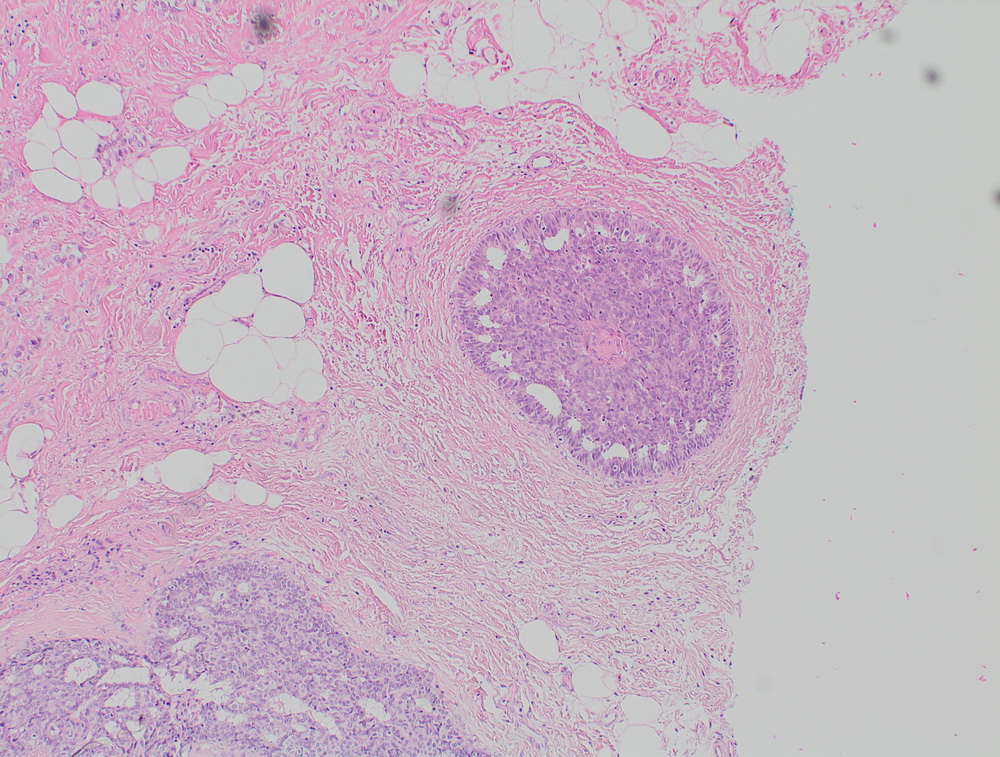

Окрашенные срезы под микроскопом

МТС крупноклеточной нейроэндокринной опухоли. |

При гистологическом исследовании биоптата и операционного материала можно оценить распространенность: размер опухоли и прорастание в окружающие ткани, насколько затронуты лимфоузлы и есть ли метастазы в отдаленные органы (если эти все структуры присланы для гистологического исследования). При консультации готовых микропрепаратов – стекол, это, как правило, невозможно, если опухоль больше размеров гистологической кассеты или рассечена предыдущим исследователем и не предоставлены данные макроскопического исследования. Во время гистологического исследования изучаются все стекла от одного образца – материала, полученного от одного вмешательства - одной операции или одной биопсии, вне зависимости от их количества, это считается одной консультацией. Сроки выполнения гистологического исследования зависят от количества микропрепаратов и от категории сложности того процесса, который в них обнаруживается, сроки могут удлиняться, особенно при необходимости использования дополнительных методов исследования и анализа дополнительных сведений. На сроки выполнения гистологического исследования влияет полнота предоставленной пациентом клинической информации, в том числе данных уже проведенных исследований.